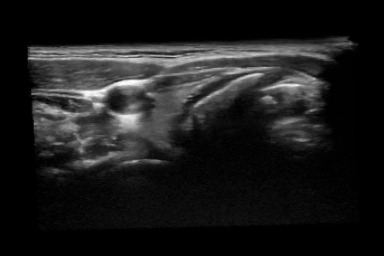

Thyroid Segmentation: The thyroid data used in this experiment has been acquired from a publicly available dataset [3] which includes freehand acquired thyroid US volumes from healthy human subjects imaged with a MHz probe. The proposed approach is compared with four different algorithms which has been reported by Narayan et. al. [1], (Table. 2). The only limitation in trying to compare commonality is that the dataset used for this comparison is not the same as the dataset used in prior art [1]. 2D visualization of segmentation is shown in Fig. 3(k) - (n) and the thyroid segmentation in the whole volume is visualized 11footnotemark: 1. Table 2 shows that our proposed frame work obtain better results than the prior art.